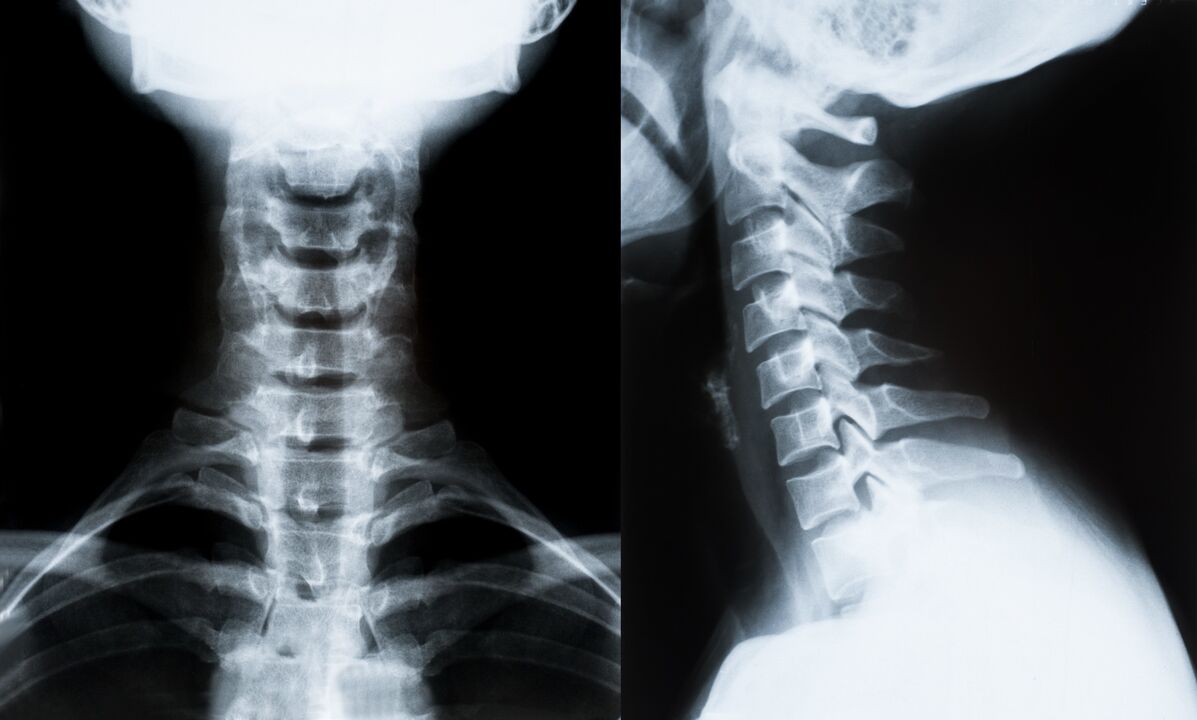

Οι κύριες μέθοδοι διάγνωσης και περαιτέρω προσδιορισμού της θεραπείας για την οστεοχονδρωσία της αυχενικής μοίρας της σπονδυλικής στήλης:

- Ακτινογραφία. Η λιγότερο αποτελεσματική, αλλά παραδοσιακή διαγνωστική μέθοδος.

- Η μαγνητική τομογραφία είναι η πιο αποτελεσματική διαγνωστική μέθοδος. Με αυτό το είδος εξέτασης του ασθενούς, όλες οι απαραίτητες δομές είναι ορατές.

- Εάν χρειάζεται να μετρηθούν οι αλλαγές, χρησιμοποιείται αξονική τομογραφία. Προσδιορίζει την παρουσία κηλών και άλλων πραγμάτων.

- Η τελευταία μέθοδος είναι η υπερηχογραφική διπλή σάρωση. Αυτή η ερευνητική μέθοδος καθορίζει την ταχύτητα της ροής του αίματος στις αρτηρίες.

Είναι αδύνατο να προσδιοριστεί με ακρίβεια η νόσος της σπονδυλικής στήλης στο σπίτι.